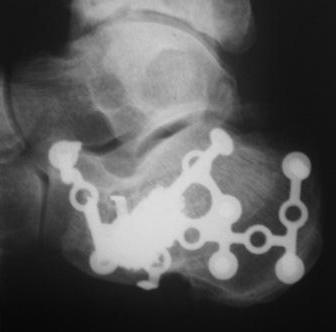

Сделали данному больному операцию. Фиксация перелома спицами. Это интраоперационный снимок.

В качестве примера у себя нашёл снимки больного оперированного около двух лет назад, функция восстановлена полностью, ходит без каких бы то нибыло нарушений, сварщик - работает в полном объёме. Не сохранился первичный снимок, можете поверить на слово перелом примерно аналогичный, как у Вашего пациента.